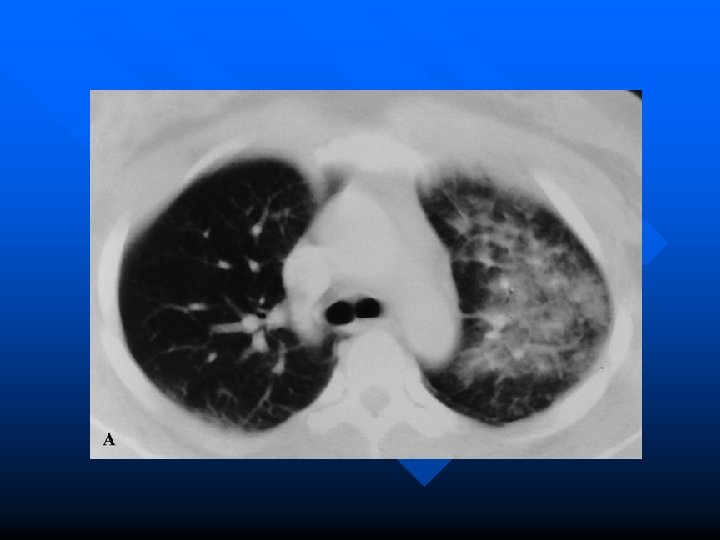

Imaging in Pulmonary Contusion n Contusion usually present on initial CXR and always appears within 6 hours Appear as patchy or diffuse airspace disease Can identify occult contusions on chest CT but clinically utility unclear – Guerro-Lopez et al. conducted a cohort study of 375 patients. One group received admission CT the other CXR. – Induced therapy changes in 30 % of patients but no effect on MV, ICU stay or mortality Guerrero-Lopez F, Vazquez-Mata G, Alcazar-Romero PP, et al. Evaluation of the utility of computed tomography in the initial assessment of the critical care patient with chest trauma. Crit Care Med 2000; 28: 1370 -5

Pulmonary Contusion vs. ARDS Contusion n Manifest within minutes (up to 6 hours) Usually confined to one lobe Apparent on initial CXR – Resolve on CXR by 48 – 72 hours n n n Development delayed Diffuse Onset between 24 -72 hours